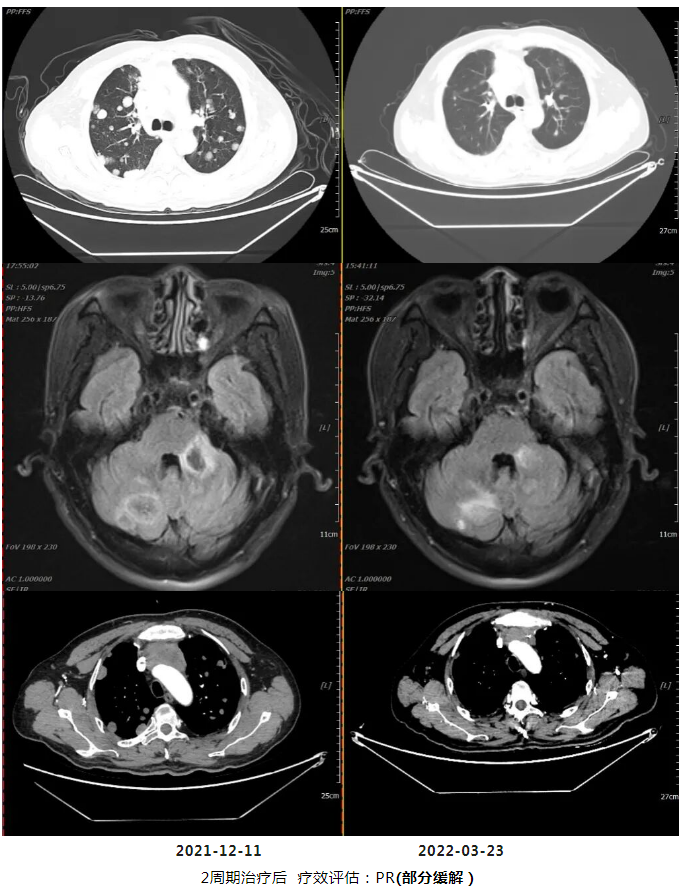

2周期化疗后复查疗效评价:PR

2021年12月11日疗效评价:PD(两肺及胸膜结节明显增多、增大;纵隔前间隙、纵隔内及两肺门转移淋巴结(现约4.7×3.5cm)较前增多、增大,上腔静脉、左头臂静脉受累狭窄;双侧小脑半球、大脑半球转移(约2.1×1.7cm)新发。